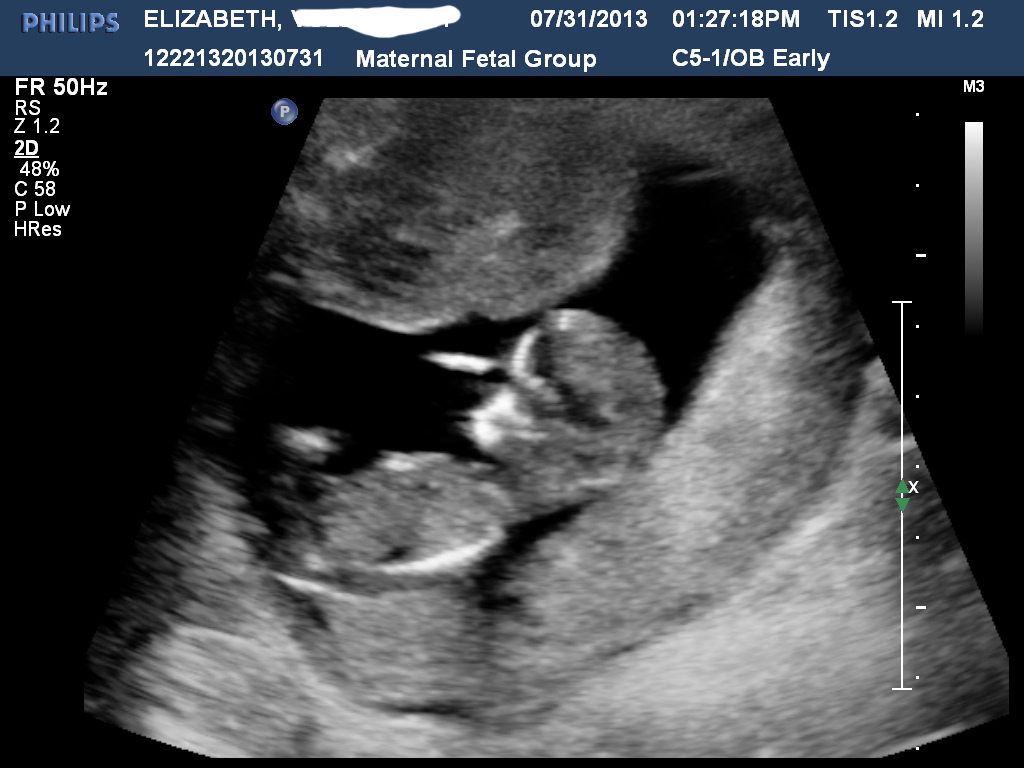

Hi all! I had my NT scan today and I'm stumped. There was no denying that my son was a boy but this baby has left me pretty stumped. I've gotten some mixed reviews elsewhere but it tends to lean one way over the other... Taken at 12w4d. So, predictions? :)

Attachment 12740